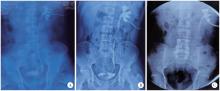

Figure 1

Stone-related ureteral strictures A, short stricture; B, long stricture; C, extensive stricture."